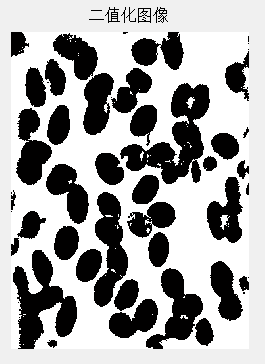

本文基于Matlab设计显微镜下血液细胞图像分割与计数系统,可以分割血液细胞图像中的多个细胞,并对分割后的细胞计数,能处理多个细胞部分重叠以及细胞位于图像边缘的特殊情况。设计步骤主要包含细胞图像预处理、图像预分割、重叠细胞分割、细胞计数等。准确的分割细胞,对于后续细胞分析很重要。分割的质量将会影响细胞图像的分析、识别与研究的正确性。因此,在医学领域,细胞分割和统计功能很重要,细胞自动识别和分析的关键困难就在于此。通过比较各种图像分割算法的优劣性,最终采用了阈值二值化分割方法分割细胞,运用分水岭算法对粘连细胞进行分开处理,每个细胞都相当于一个连通域,经过计算连通域的数目,即可得到图像中细胞的个数。

如果取(黑色区域),(白色区域),这就是图像的二值化。